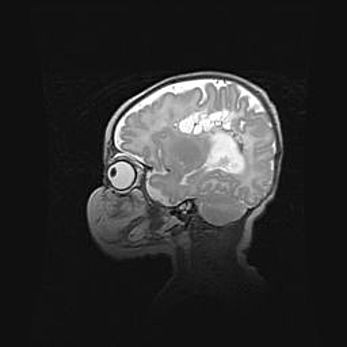

Церебральная ишемия II.

Возраст: 5 дней

Вес: 3400 г

Пол: женский

Окружность головы: 35 см

Срок гестации: 39 недель

Церебральная ишемия – это заболевание, характеризующееся недостаточностью (гипоксией) либо полным прекращением (аноксией) снабжения мозга кислородом по причине закупорки одного или нескольких сосудов. Это приводит к  что метаболическим расстройствам различной степени тяжести в тканях головного мозга, развитию коагуляционных некрозов и гибели нейронов.